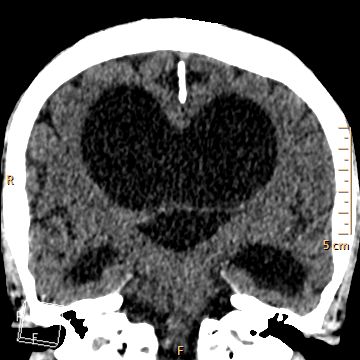

Coeur coupes TDM

Encéphale coupes TDM